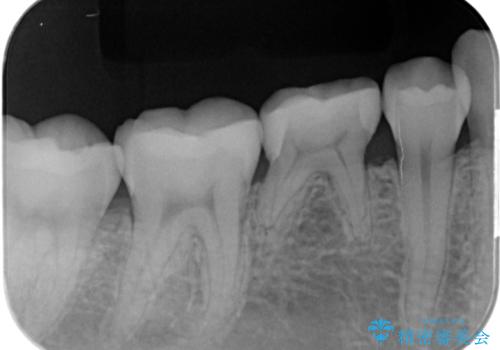

- 歯が染みるとの事で来院。

レントゲンを撮影したところ虫歯がありましたので拡大鏡下で虫歯を取り除いた後、e-maxインレーにて治療を行いました。